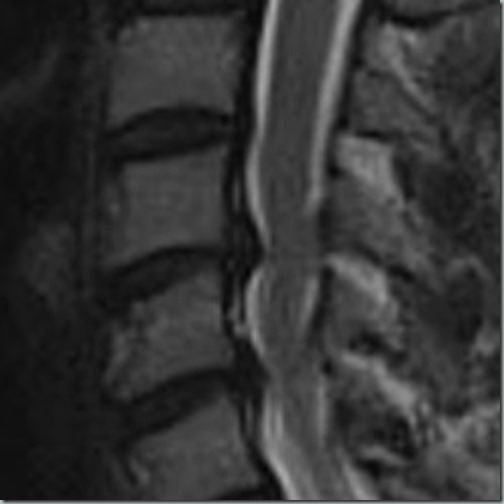

09112023

Von oben/vorne ran, Bandscheiben raus, beim Kreis fräsen (das ist die Nervenwurzel, die gerade bedrängt wird), das Viereck – den Cage – einsetzen und im Bild links hat sie eingezeichnet, wo das ganze theoretisch verschraubt werden soll. Je nach Knochenqualität evtl. auch mit einsetzen einer Metallplatte.

09112023II